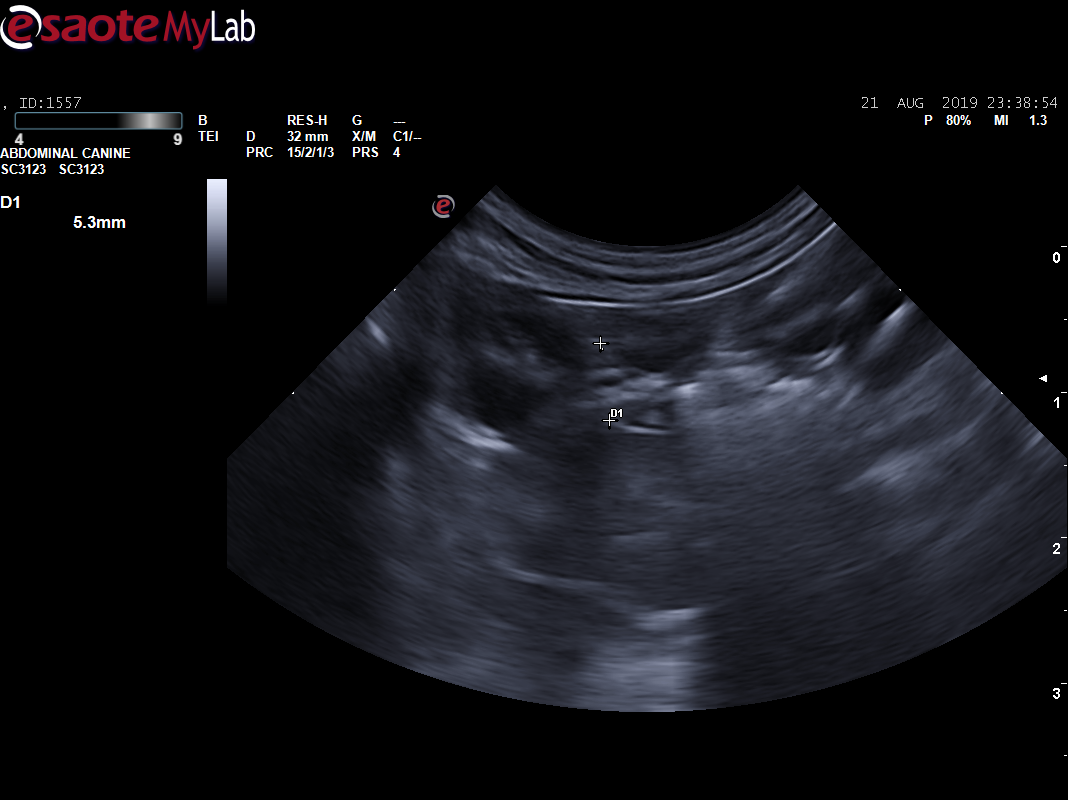

经过5天住院治疗,住院期间患猫少量进食,未见呕吐、腹泻,多尿,水和良好,但仍有腹痛感。复查CBC,提示炎症未见下降;基础生化,提示应激;胸腔X线片,未出现转移情况,建议手术切除肿物送检。

B超显示:脾脏弥散性低回声(鉴别肥大细胞瘤、淋巴瘤、充血等),腹部肿物(鉴别淋巴瘤、肥大细胞瘤、肉瘤),肾脏(鉴别肾小球肾炎、慢性肾炎)。